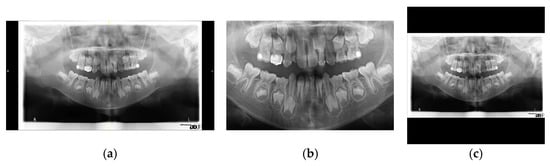

2.1. Image Preprocessing

2.1.1. Image Normalization

2.1.2. Image Enhancement